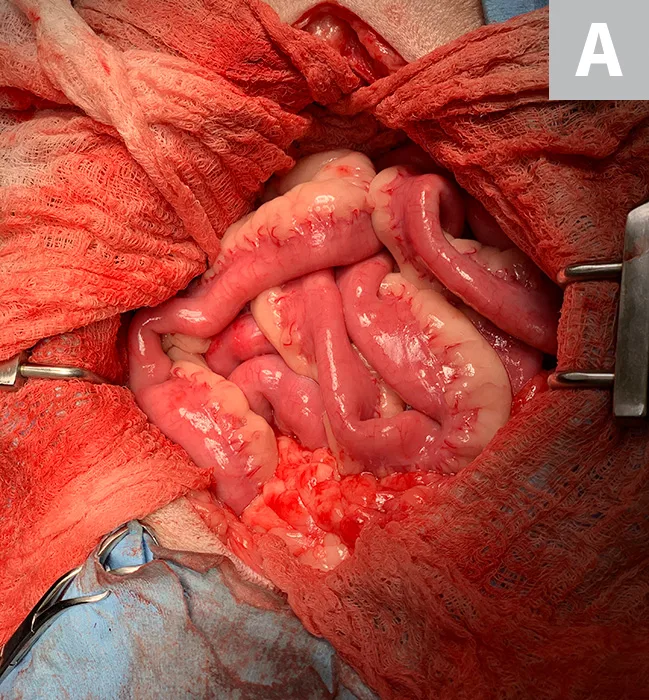

Treatment of intestinal intussusception involves laparotomy with manual reduction if the affected segment appears potentially viable and/or resection and anastomosis of the affected intestinal segment if neoplasia is the underlying cause or if the affected segment is necrotic or cannot be reduced (Figures 2-4).

FIGURE 2

A portion of intestine after intussusception reduction. There is serosal tearing (short arrow) and significant erythema (long arrow).